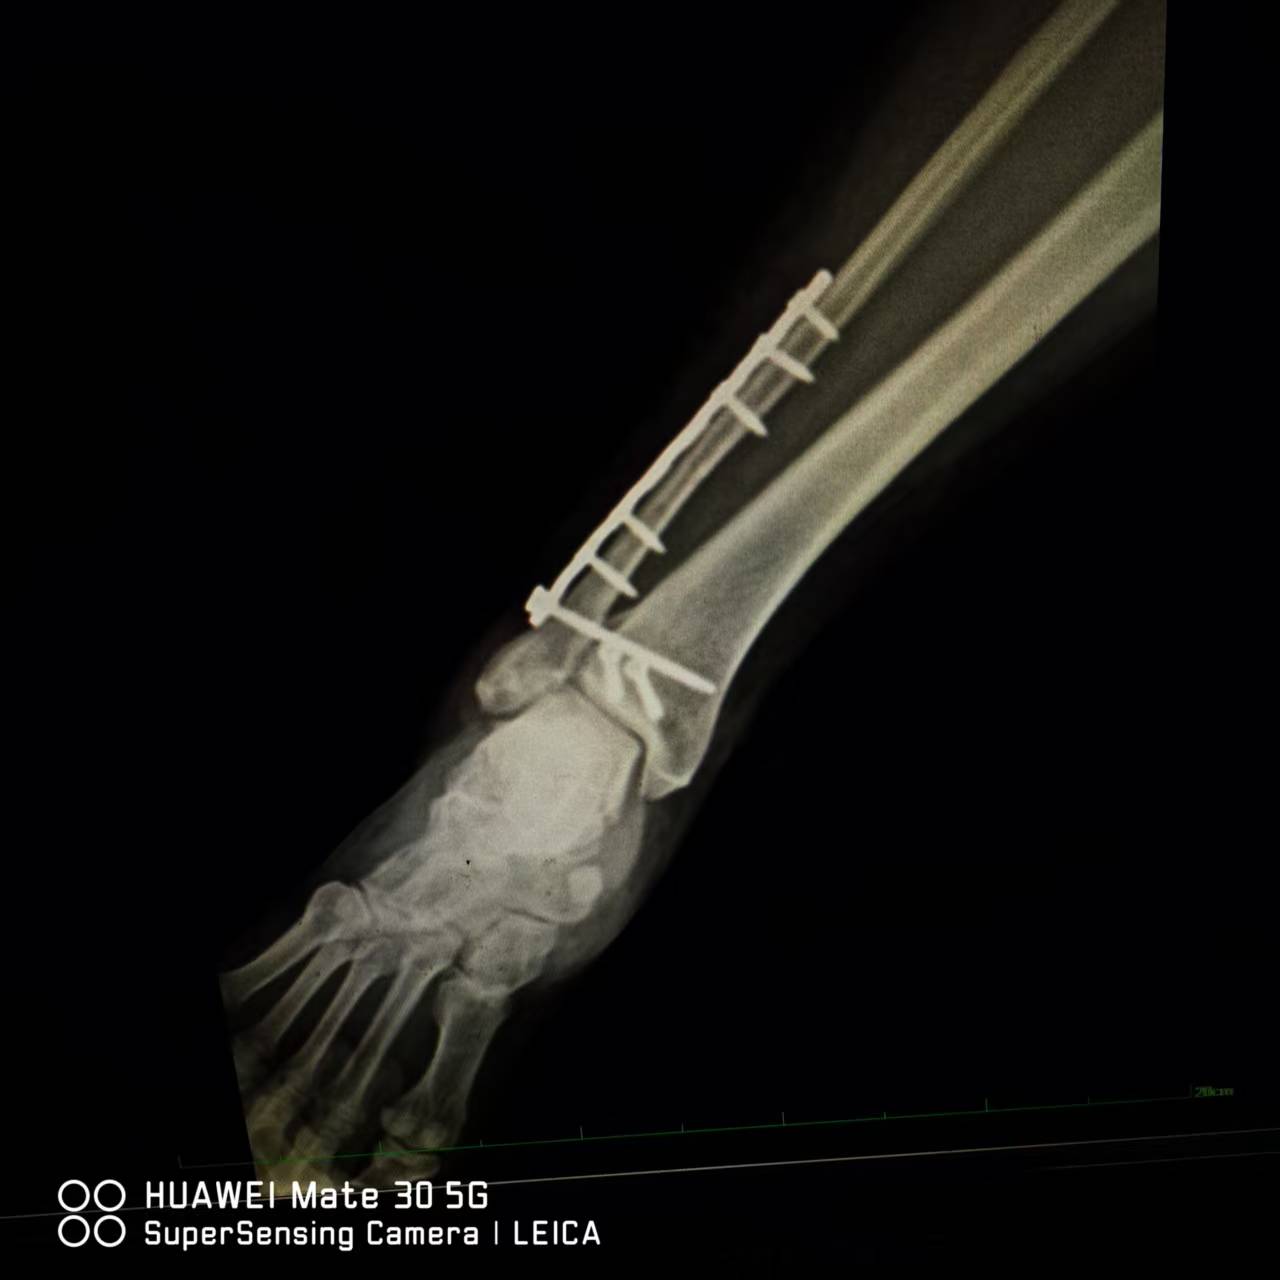

8月14日上午,董庆武主任带领骨科团队,在全麻麻醉下,为患者行右外踝切开复位锁定钛板螺钉内固定,后踝切开复位拉力螺钉内固定,术中,专家团队凭借精湛医术和丰富经验,精准地对骨折部位进行复位和固定,术后摄片效果满意。